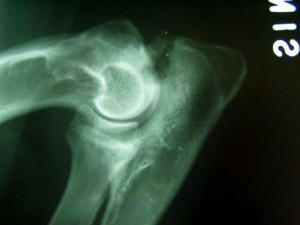

Snímek lokte postiženého těžkou artrózou: